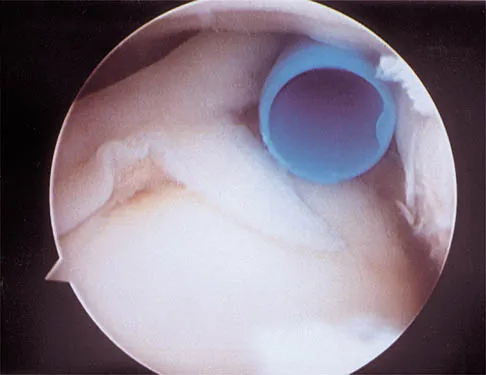

Figure 43 shows an arthroscopic view of a right shoulder through a lateral portal in the beach chair position. The arrow is pointing to what structure?

Explanation

This view from the lateral portal shows a full-thickness rotator cuff tear. The glenohumeral joint can be visualized through this tear. The glenoid, labrum, and biceps tendon attaching to the superior aspect of the glenoid are easily viewed from this portal, and the arrow is pointing to the biceps tendon. Arthroscopic rotator cuff repair can be performed while visualizing from this portal and using anterior and posterior working portals. Mazzocca AD, Noerdlinger M, Cole B, et al: Arthroscopy of the shoulder: Indications and general principles of techniques, in McGinty JB (ed): Operative Arthroscopy, ed 3. Philadelphia, PA, Lippincott Williams & Wilkins, 2003, pp 412-427.